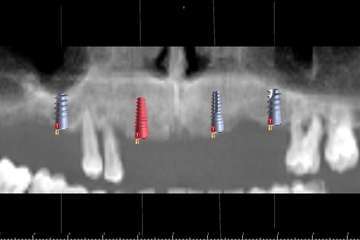

Cirugía guíada por ordenador

El doctor Juan Carlos Rodríguez Pascuas especialista en cirugía de la clínica explica a continuación como funciona y en qué consiste el sistema de cirugía guiado por ordenador:

-Existe un gran abanico de posibilidades para reponer los dientes perdidos con implantes, desde la colocación de unos pocos implantes para reponer todos los dientes, hasta la colocación de implantes y dientes provisionales en el mismo día. Nuestra intención es ofrecer a cada paciente lo que mejor se adapte a su situación. Para ello aprovechamos las últimas tecnologías disponibles, como la Cirugía Guiada por ordenador. Así, el paciente puede ver previamente las opciones que tiene y decidir qué tipo de tratamiento prefiere.

-No tiene por qué serlo. Con los avances tecnológicos que tenemos a disposición, podemos hacer cirugías mínimamente invasivas guiadas por ordenador, que en muchos casos no necesitan ni siquiera puntos de sutura. Durante el tratamiento el paciente no siente ningún dolor y con la adecuada ayuda farmacológica y unos pocos cuidados, en la gran mayoría de los casos no hay ni molestias ni inflamación después de la cirugía.